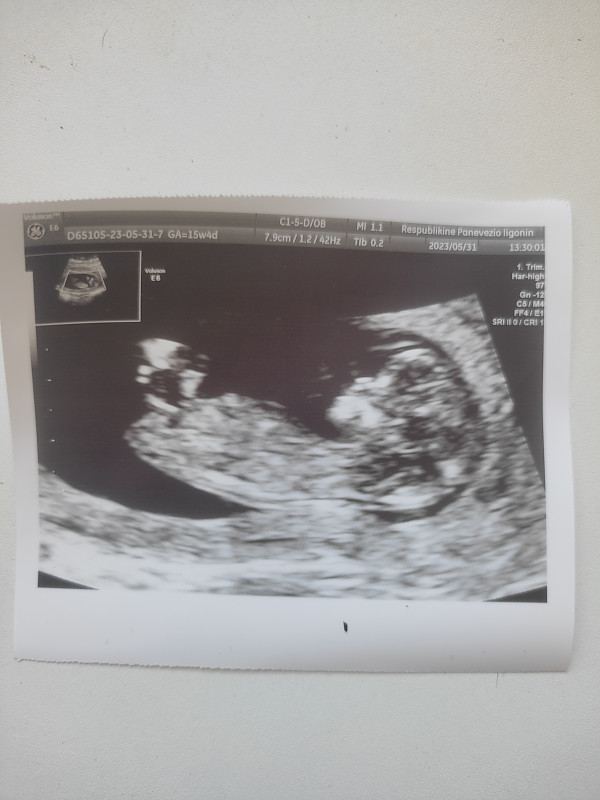

Ramzio vaisiaus lyties nustatymo teorija

Pagal Ramzio teoriją kūdikio lytį galima nustatyti labai anksti, 6-8 nėštumo savaitę iš pradėjusios formuotis placentos vietos. Skaityti visą straipsnį